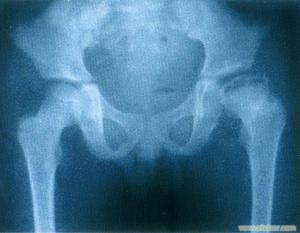

2.第2期 X線平片有陽性所見,顯示不典型的特發性股骨頭壞死徵象,但關節軟骨下骨板正常

3.第3期 呈特異性改變健康搜尋,顯示股骨頭前外方楔形骨硬化有斑點狀骨質疏鬆,軟骨下有梗死或透亮線健康搜尋股骨頭失去其正常圓球形。

4.第4期 X線平片顯示晚期變化此時股骨頭明顯變形關節間隙狹窄或消失。

本病的診斷主要依據慢性病史、臨床表現及影像學檢查健康搜尋尤其是後者,健康搜尋不僅有利於本病的診斷與鑑別診斷對病情的判定與分期治療方法的選擇及預後判定等均至關重要根據X線平片所見可對成人骨壞死進行分期。但病因不同其分期亦不一致,且各專家健康搜尋的意見亦不統一。鑑別診斷